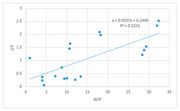

| 10:59, 4 August 2023 | Valore di aspettazione.jpg (file) |  |

2.57 MB | Gianni | 1 | |